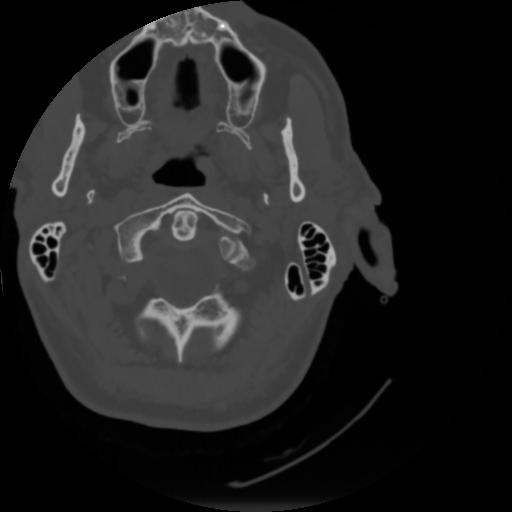

4 CEREBRO,,Vol,0.5,CEREBRO,,